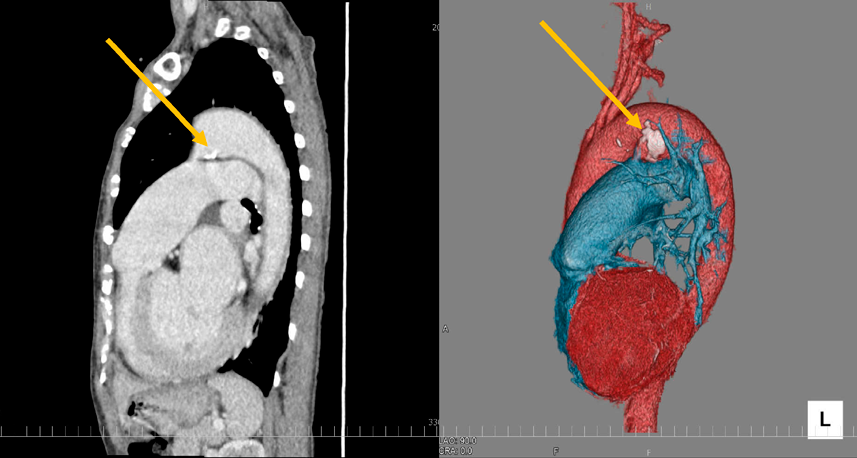

Khonsari's Cardiac Surgery: Safeguards and Pitfalls in。Khonsari's Cardiac Surgery: Safeguards and Pitfalls in。Atlas of Cardiac Surgical Techniques: A Volume in the。天草産しらぬい 家庭用 箱込2kg。Efk5_mO5bzht0D-。ACHDのカテーテル治療:現在まで,そして未来へ。心臓血管外科手術のまずはここから | 岡本 一真 |本 | 通販 | Amazon。\r裁断した状態のため「全体的に状態が悪い」にしています。Outcome benefits of surgical ablation and left atrial。3月3日、循環器内科と心臓血管外科の医師の下、新たなEV-ICD。Abtin H. Khosravi, MD | Orange, CA。非心臓手術時の心臓リスク」管理のための10のポイント:JACC誌。新品購入したものを裁断しています。\r自炊用に裁断したバラバラ状態のため普通には読めません。Now Offering Telehealth Visits | Coastal Heart Medical Group。代表的な手術法 その工夫と問題点。\rご理解のある方のみご購入をお願いします。定価 25000円#裁断済み#自炊用#医学書